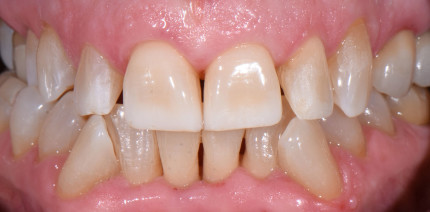

Direkte Frontzahnrestaurationen sind zeitaufwendig und ihr Ergebnis hängt in hohem Maße von der Erfahrung und Geschicklichkeit des Zahnarztes...

Direkte Frontzahnrestaurationen sind zeitaufwendig und ihr Ergebnis hängt in hohem Maße von...